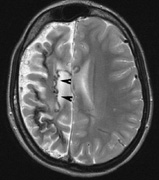

- Cognitive impairment. Thirty percent to 60% of children with NF1 have learning difficulties, which

are typically mild and nonprogressive. These include visual-spatial

problem-solving difficulty, language disorders, and attention

deficit disorder. The reason for this is not clear but may be related

to unidentified bright objects (UBOs) seen on T2-weighted

brain magnetic resonance imaging (MRI) scans. These hyperintensities

are common in young patients with NF1 but decrease with advancing

age. The histopathologic correlate of UBOs is unclear. It has

been postulated that the prevalence of learning difficulties in children

with NF1 may be related to heterozygosity of the NF1 gene (i.e., the gene may have additional functions that affect cognition when the

full complement of its gene product is not expressed in the central nervous

system).25,32–34